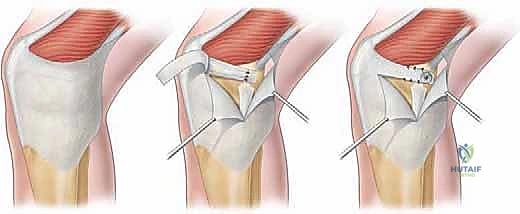

Step 4: Suture Placement into the MPFL and Patellar Fixation

"Now for the repair itself. We'll use robust, non-absorbable sutures to secure this."

- Suture Placement into MPFL: Using a strong, non-absorbable suture (e.g., 2-0 FiberWire or similar), we will place multiple locking-loop or Krackow sutures into the substance of the avulsed MPFL tissue.

- Pearl: Ensure you capture a good amount of healthy ligamentous tissue with each stitch to prevent pull-out. Typically, 2-3 strong sutures are sufficient, spaced evenly across the avulsed edge.

- Anchor Placement: We will now place two small, fully threaded suture anchors into the medial border of the patella.

- Drill Hole Preparation: Using a drill guide, create pilot holes for the anchors. Aim for the superior and inferior aspects of the MPFL footprint on the patella.

> Drill under constant direct visualization. Ensure the drill bit does not penetrate the articular surface of the patella. The patella is a relatively thin bone, and intra-articular penetration can cause significant chondral damage. - Anchor Insertion: Insert the suture anchors securely into the drilled holes, ensuring they are flush with the bone surface.

- Pearl: Predrill the anchor holes carefully. Test the security of the anchors after insertion with a gentle tug. They should be absolutely rock-solid.

Intraoperative view illustrating the placement of suture anchors into the medial patellar facet, preparing for MPFL reattachment.

Close-up view of the suture anchors securely placed into the patella, with sutures ready for passage through the avulsed MPFL.